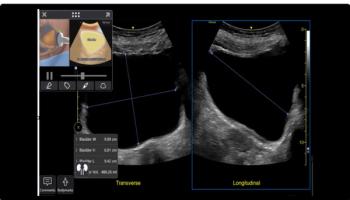

A 9-year-old male presents with acute onset abdominal pain with fever, vomiting, and diarrhea. His abdomen on exam was mildly distended and diffusely tender to palpation, especially in the right upper quadrant and right lower quadrant.

Ultrasound demonstrates a blind ending tubular structure in the right lower quadrant measuring approximately 1 cm in luminal diameter.